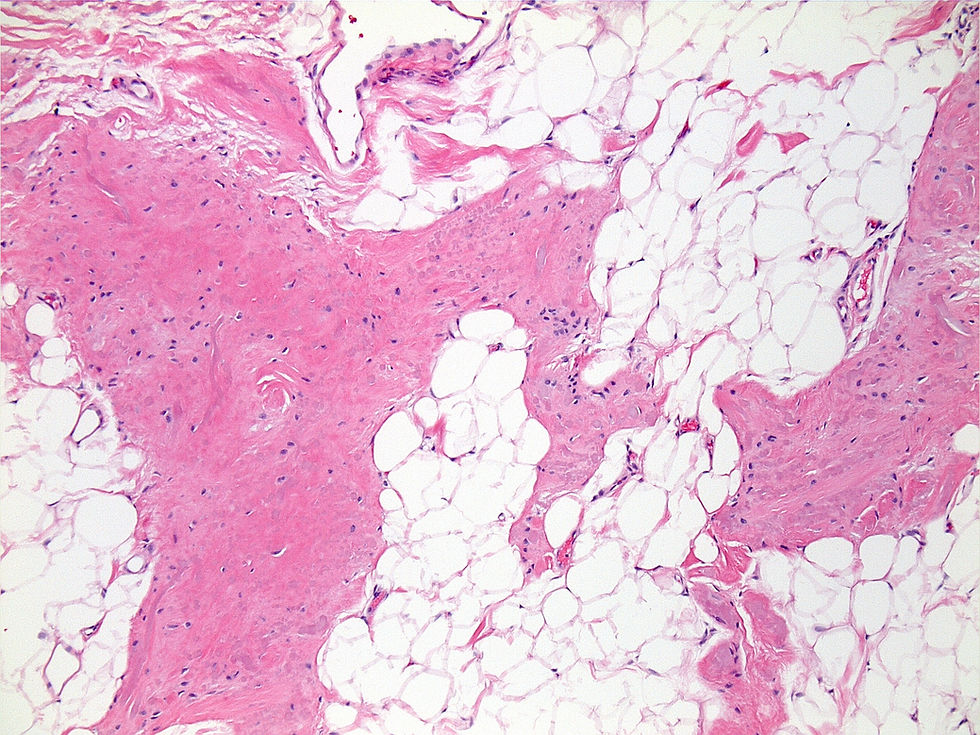

This is a poorly-circumscribed subscapular mass from a 53-year-old woman. Thanks again to Dr. Denham for sharing these cases...